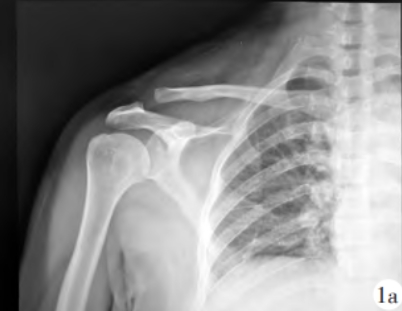

Новые возможности лечения вывиха акромиально-ключичного сустава — три метода внутренней фиксации

Вывих акромиально-ключичного сустава - одна из наиболее частых травм плеча. Чаще встречается вследствие прямого наси···